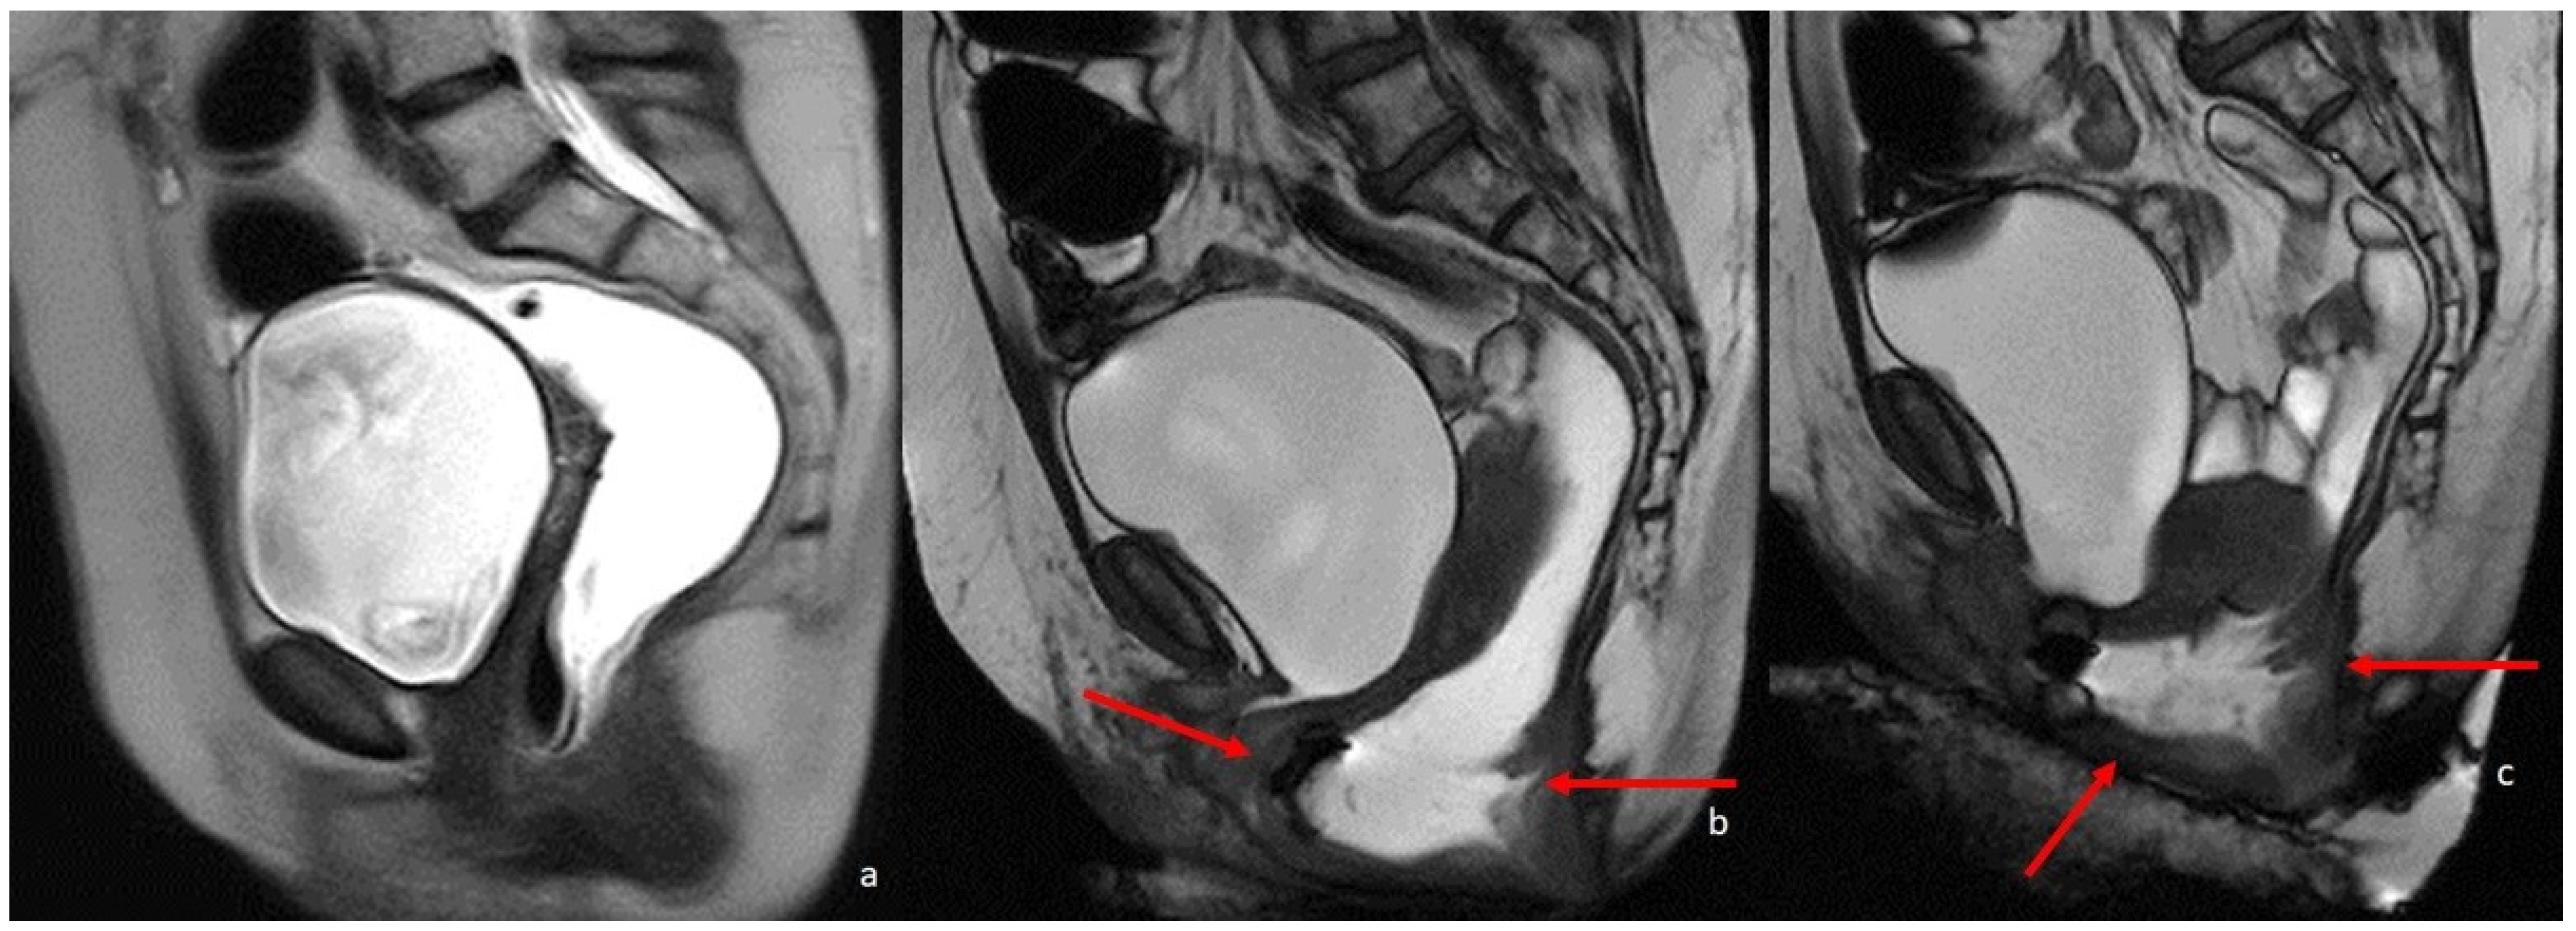

Nowadays, MR defecography allows a real-time visualization of the same parameters, by using a rectal contrast agent (usually ultrasound gel) to distend and visualize the rectum; dynamic images are taken during straining, squeezing, and defecation, similarly to conventional defecography [51,52,53] (Figure 5).

Figure 5.

MRI defecography sagittal T2-weighted images with endoluminal US gel, in a 62-year-old female with severe stipsis. (a) is rest phase, (b) is a straining phase (the arrows indicate a severe prolapse posterior compartment with invagination and anterior rectocele; mild prolapse of middle and anterior pelvic compartments), (c) is in evacuation phase (showing severe three-compartment pelvic prolapse with rectal invagination and anterior rectocele cystocele and colpocele (grade III)).